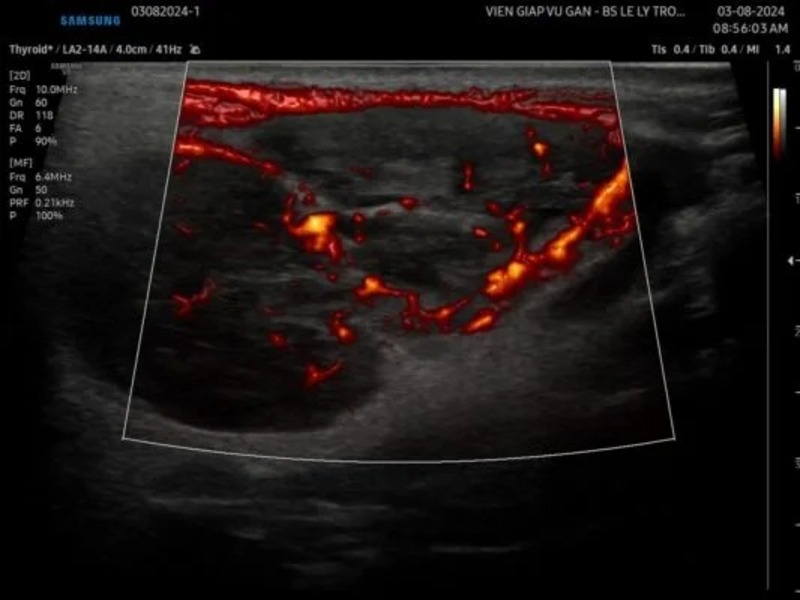

SIÊU ÂM (Máy Samsung V8) : Tuyến mang tai hai bên,

• Bên trái, thùy nông, ⅔ dưới có cấu trúc echo kém xen lẫn echo dày không đồng nhất, bên trong có hóa nang, bờ đa cung, tăng âm phía sau nhẹ, bờ đều, giới hạn rõ, kt# 40x30mm mạch máu phân bố rải rác khắp bướu. Siêu âm đàn hồi định lượng 25-35 kPa.

• Bên phải thùy nông, ⅔ dưới có hai cấu trúc tượng tự nằm sát nhau tổng kt #50x40mm.